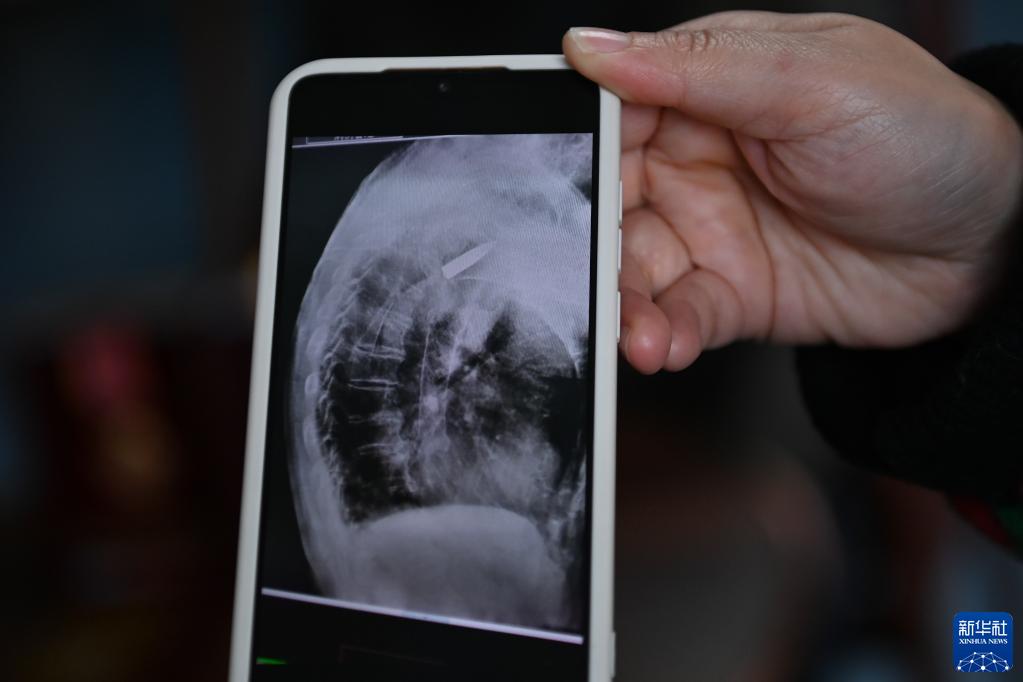

医院的放射线视觉指引图像显示,罗锦文老人右侧肩膀里有一颗长约3.5厘米的子弹(3月2日摄)。新华社记者 黄宗治 摄

2022年11月11日上午,浙江省平湖市第一人民医院,消化科内镜室主任医师王明友正在为一位吞咽困难的96岁老人做食道支架置入手术。突然,医生的眉头紧皱起来:在X射线下,发现老人右侧肩膀里居然有一颗长约3.5厘米的子弹!

2022年,平湖市第一人民医院在给老人做食道支架置入手术时,X射线下清晰地看到老人肩膀里有颗长约3.5厘米的子弹。而这颗子弹,早已与老人的骨头粘在了一起,无法取出。